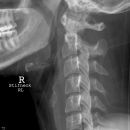

Densfraktur

Foramen arcuale bzw Kimmerle Anomalie